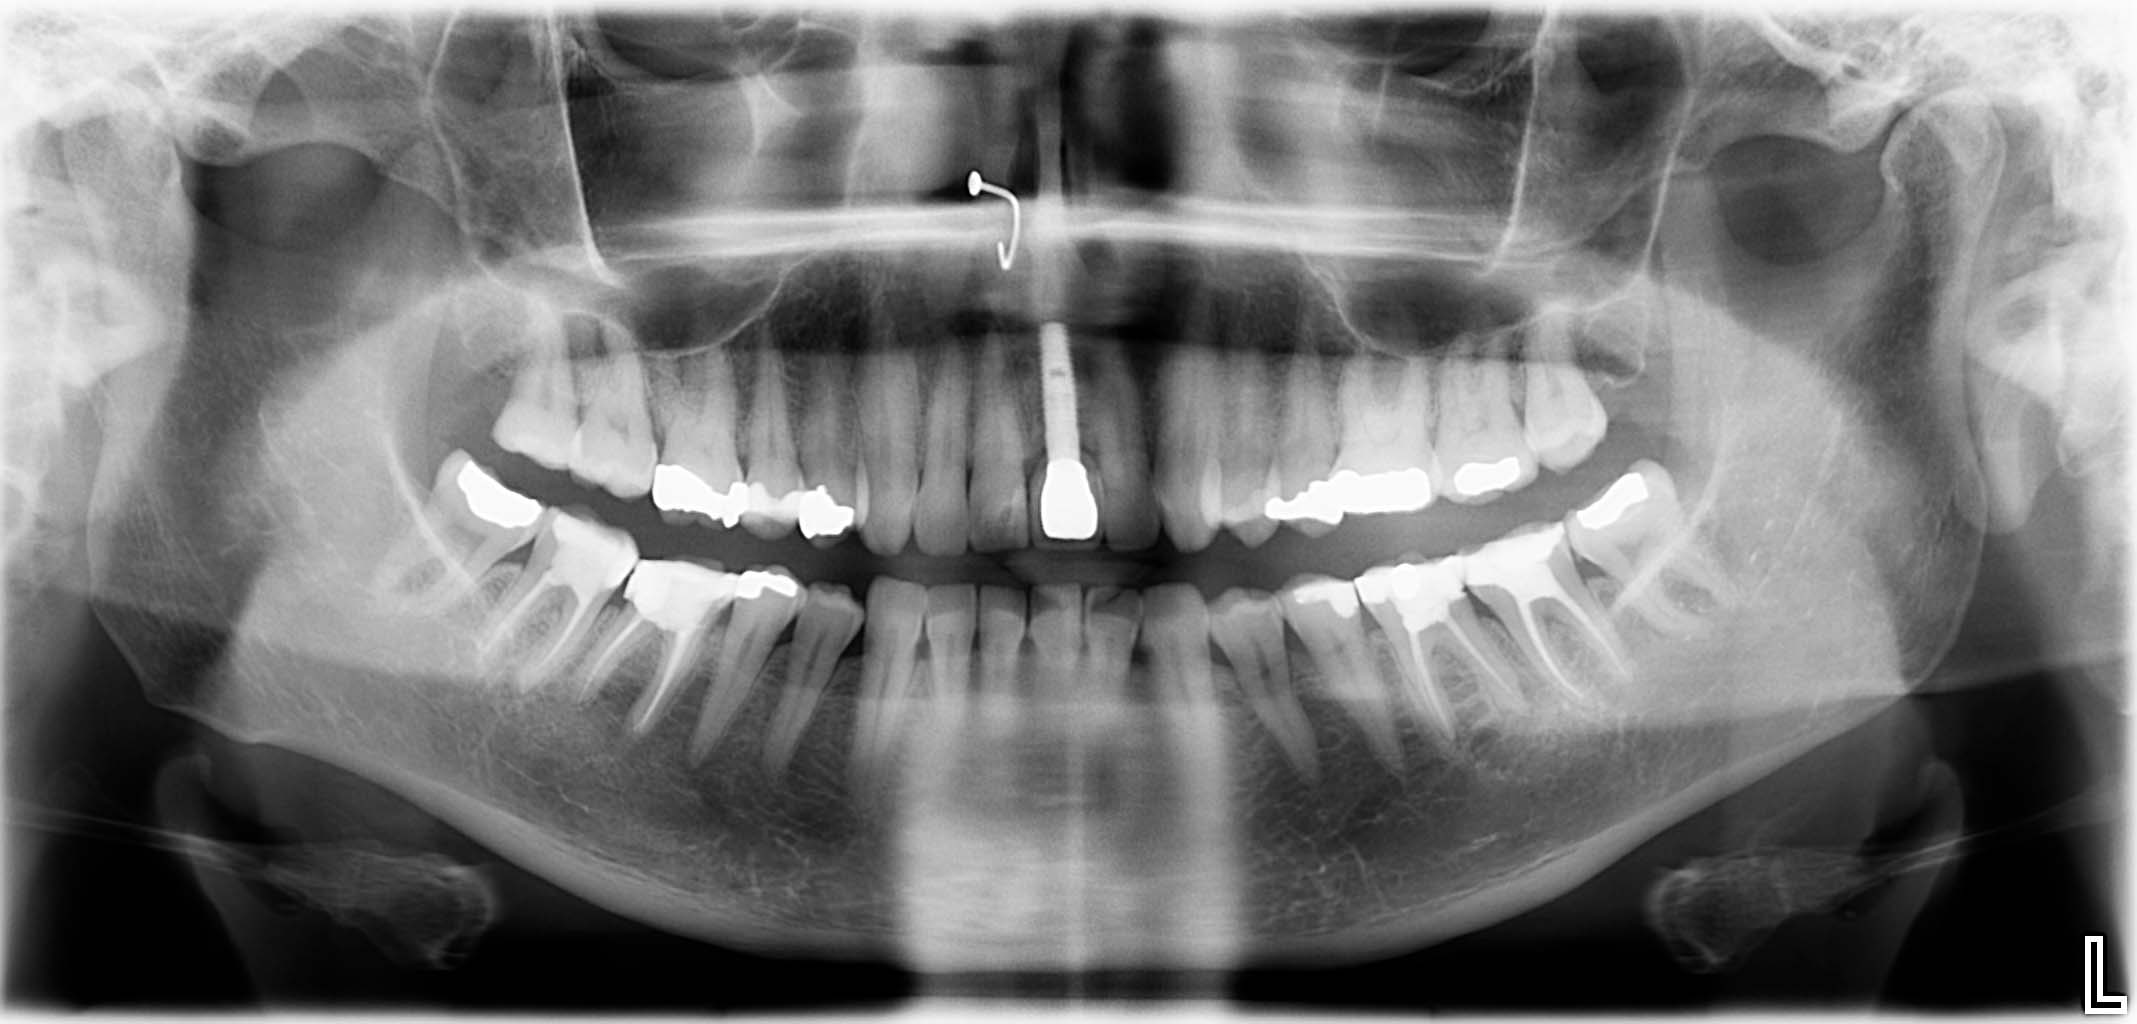

Ausgangssituation: Zahn 36 mit apikaler Beherdung, nicht erhaltungswürdig